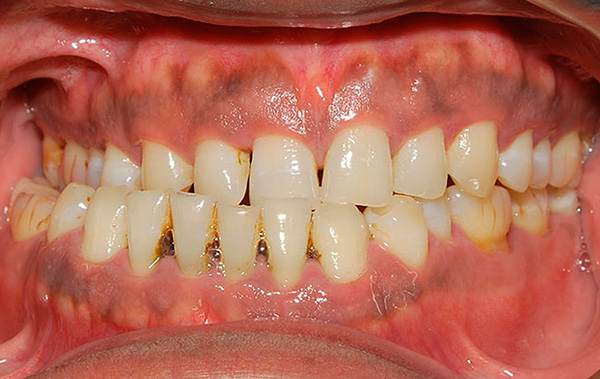

A foto abaixo mostra exemplos de mordida cruzada em uma criança e um adulto:

Tipos de mordida cruzada por ortodontistas